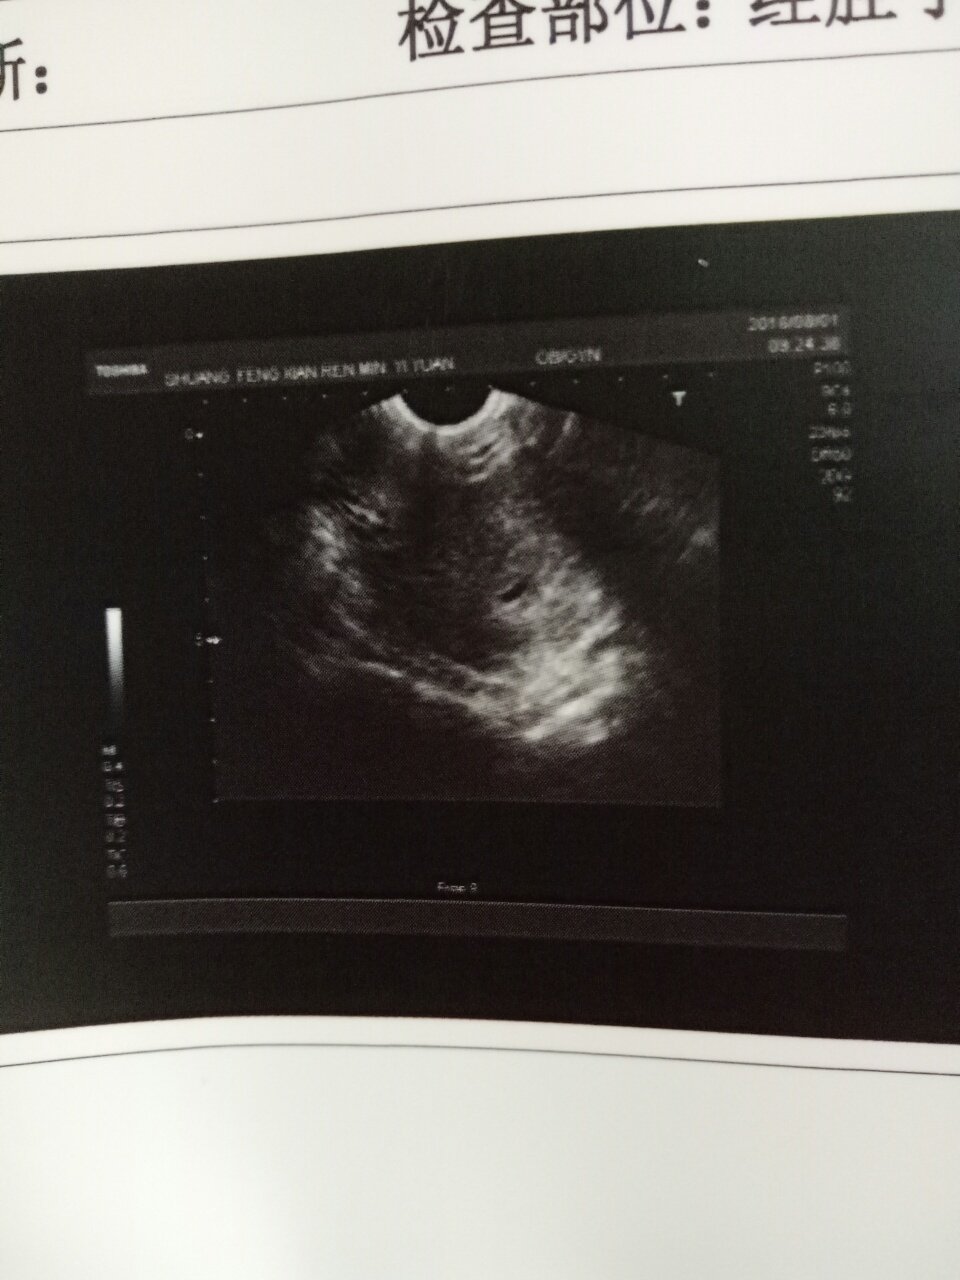

怀孕48天做b超,超声所见,前位子宫,大小58*45*44mm,宫颈长约26mm,子宫形态正常,轮廓清晰,表面光滑,肌层回声均匀,宫腔内探及7*7*5 mm的无回声暗区,周边回声偏强,内未见卵黄囊回声,双侧附件区暂未见明显肿块,包块回声,盆底未见明显液性暗区。这个正常嘛?